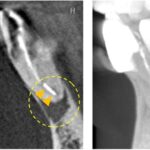

右上6番は、近心根管のパーフォレーション(穿孔)が疑われ、そこから根尖孔外へレントゲン的に白く写る不透過性物質の押し出しが確認できました。性状から、貼薬材料あるいは根管充填に使用するシーラーであると推測されました。

CT画像による三次元的比較

CT画像上でも、根尖部の骨の回復と漏出していた材料の消失が認められます。